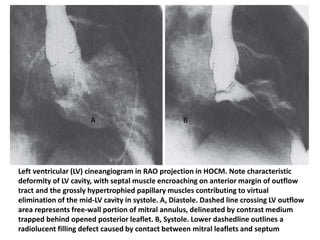

Left ventricular (LV) cineangiogram in RAO projection in HOCM. Note characteristic

deformity of LV cavity, with septal muscle encroaching on anterior margin of outflow

tract and the grossly hypertrophied papillary muscles contributing to virtual

elimination of the mid-LV cavity in systole. A, Diastole. Dashed line crossing LV outflow

area represents free-wall portion of mitral annulus, delineated by contrast medium

trapped behind opened posterior leaflet. B, Systole. Lower dashedline outlines a

radiolucent filling defect caused by contact between mitral leaflets and septum